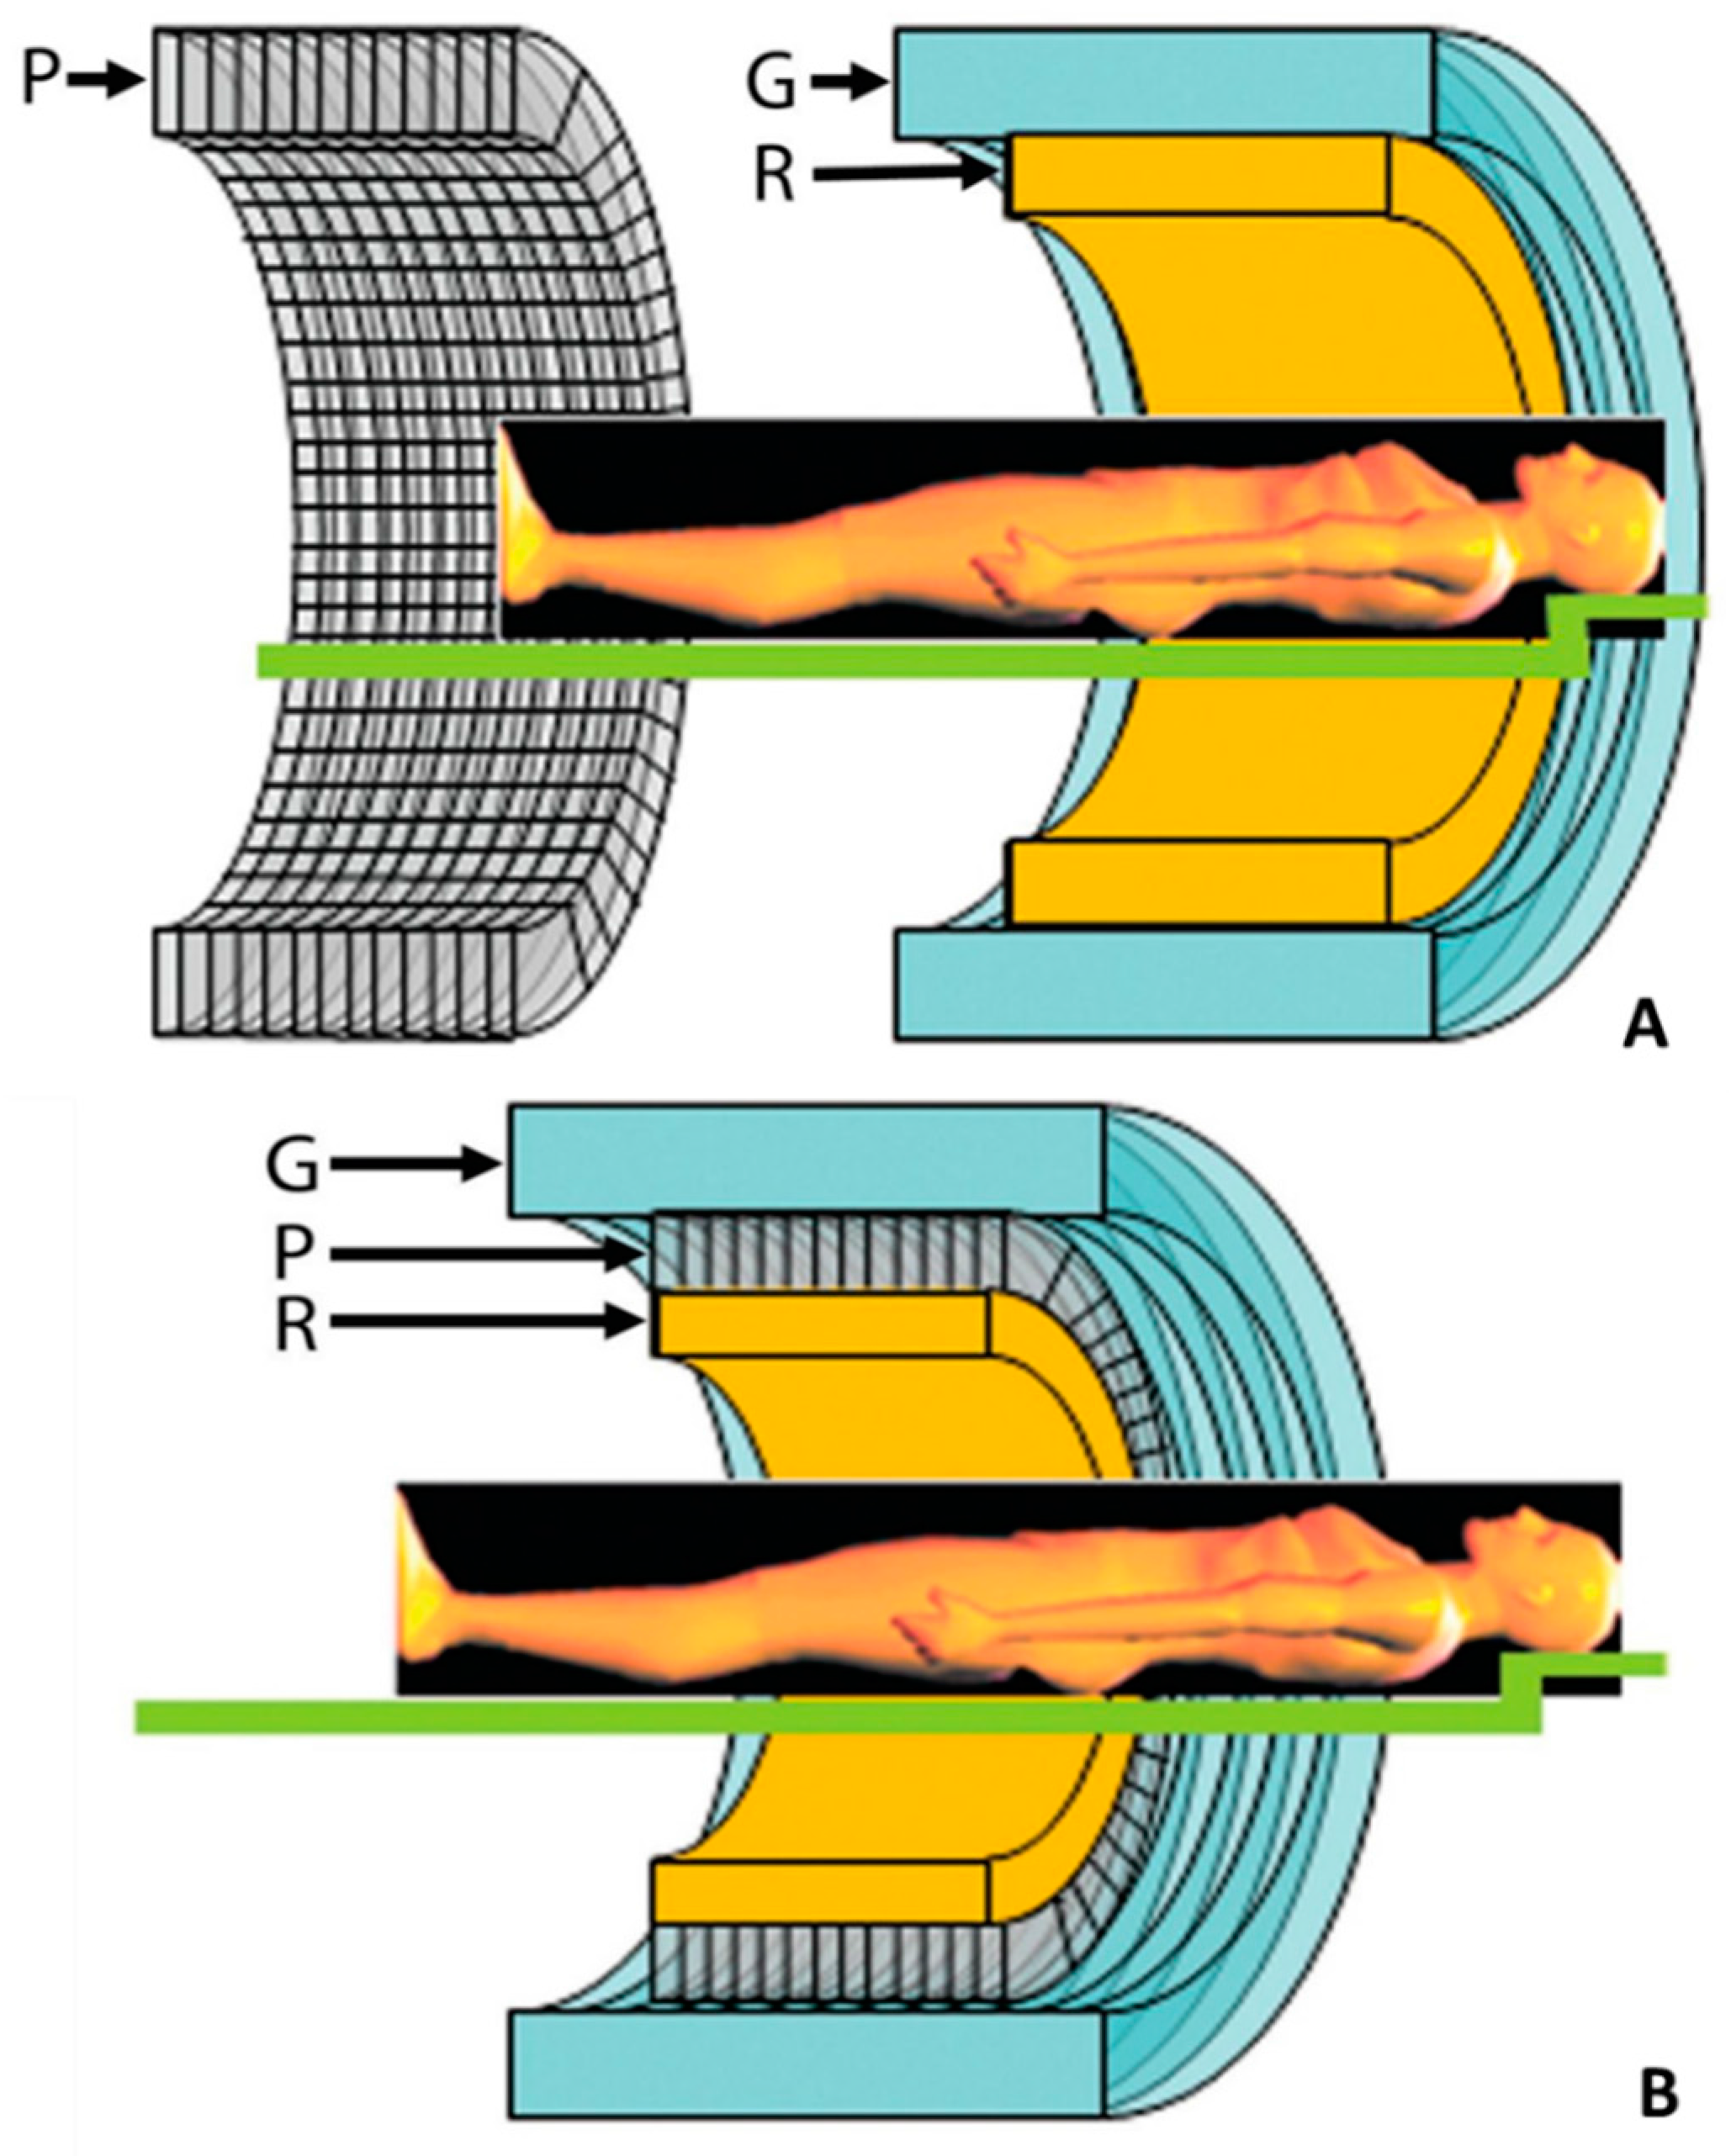

2.2. PET/CMR Technology